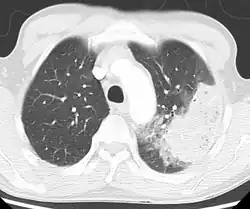

A chest radiograph is frequently used in diagnosis.[23] In people with mild disease, imaging is needed only in those with potential complications, those not having improved with treatment, or those in which the cause is uncertain.[23][69] If a person is sufficiently sick to require hospitalization, a chest radiograph is recommended.[69] Findings do not always match the severity of disease and do not reliably separate between bacterial and viral infection.[23]

X-ray presentations of pneumonia may be classified as lobar pneumonia, bronchopneumonia, lobular pneumonia, and interstitial pneumonia.[75] Bacterial, community-acquired pneumonia classically show lung consolidation of one lung segmental lobe, which is known as lobar pneumonia.[42] However, findings may vary, and other patterns are common in other types of pneumonia.[42] Aspiration pneumonia may present with bilateral opacities primarily in the bases of the lungs and on the right side.[42] Radiographs of viral pneumonia may appear normal, appear hyper-inflated, have bilateral patchy areas, or present similar to bacterial pneumonia with lobar consolidation.[42] Radiologic findings may not be present in the early stages of the disease, especially in the presence of dehydration, or may be difficult to interpret in the obese or those with a history of lung disease.[24] Complications such as pleural effusion may also be found on chest radiographs. Laterolateral chest radiographs can increase the diagnostic accuracy of lung consolidation and pleural effusion.[41]

A CT scan can give additional information in indeterminate cases[42] and provide more details in those with an unclear chest radiograph (for example occult pneumonia in chronic obstructive pulmonary disease). They can be used to exclude pulmonary embolism and fungal pneumonia, and detect lung abscesses in those who are not responding to treatments.[41] However, CT scans are more expensive, have a higher dose of radiation, and cannot be done at bedside.[41]